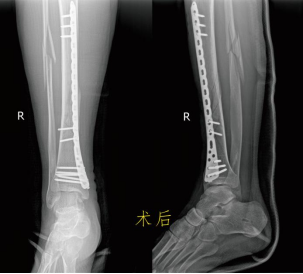

患者何某,41歲,月前因騎電動車時不慎摔倒,導致右小腿腫痛、活動受限,皮膚破裂流血不止,由120送至市一醫院經開區院區。攝DR顯示脛腓骨中下段螺旋型粉碎性骨折,骨折端明顯重疊移位。入院診斷:1.開放性脛骨下端骨折(右,粉碎性),2.腓骨骨折(右,粉碎性),3.小腿開放性傷口(右),4.高血壓。骨科醫師接診后立即在局麻下給患者進行右跟骨牽引術,起到矯正骨折畸形、恢復脛腓骨的長度及維持骨折的臨時穩定作用。經過治療處理,患者隨即表示疼痛緩解了很多,隨后在局部麻醉下對開放傷口進行了清創處理。 待患者右小腿開放傷口愈合后,檢查沒有發現紅腫熱痛、血常規白細胞增高等感染征象,進行脛骨骨折微創切開復位鋼板螺釘植入內固定。術后患者拆線出院,定期來院復查,2個月后逐步下地負重站立及行走,3個月可正常行走。

近期,何某再次來到了醫院門診復查DR片示脛腓骨折內固定術后,骨折線消失,骨折端大量骨痂生長。入住骨科,完善術前準備后,取出了鋼板螺釘,術后10天患者順利出院。